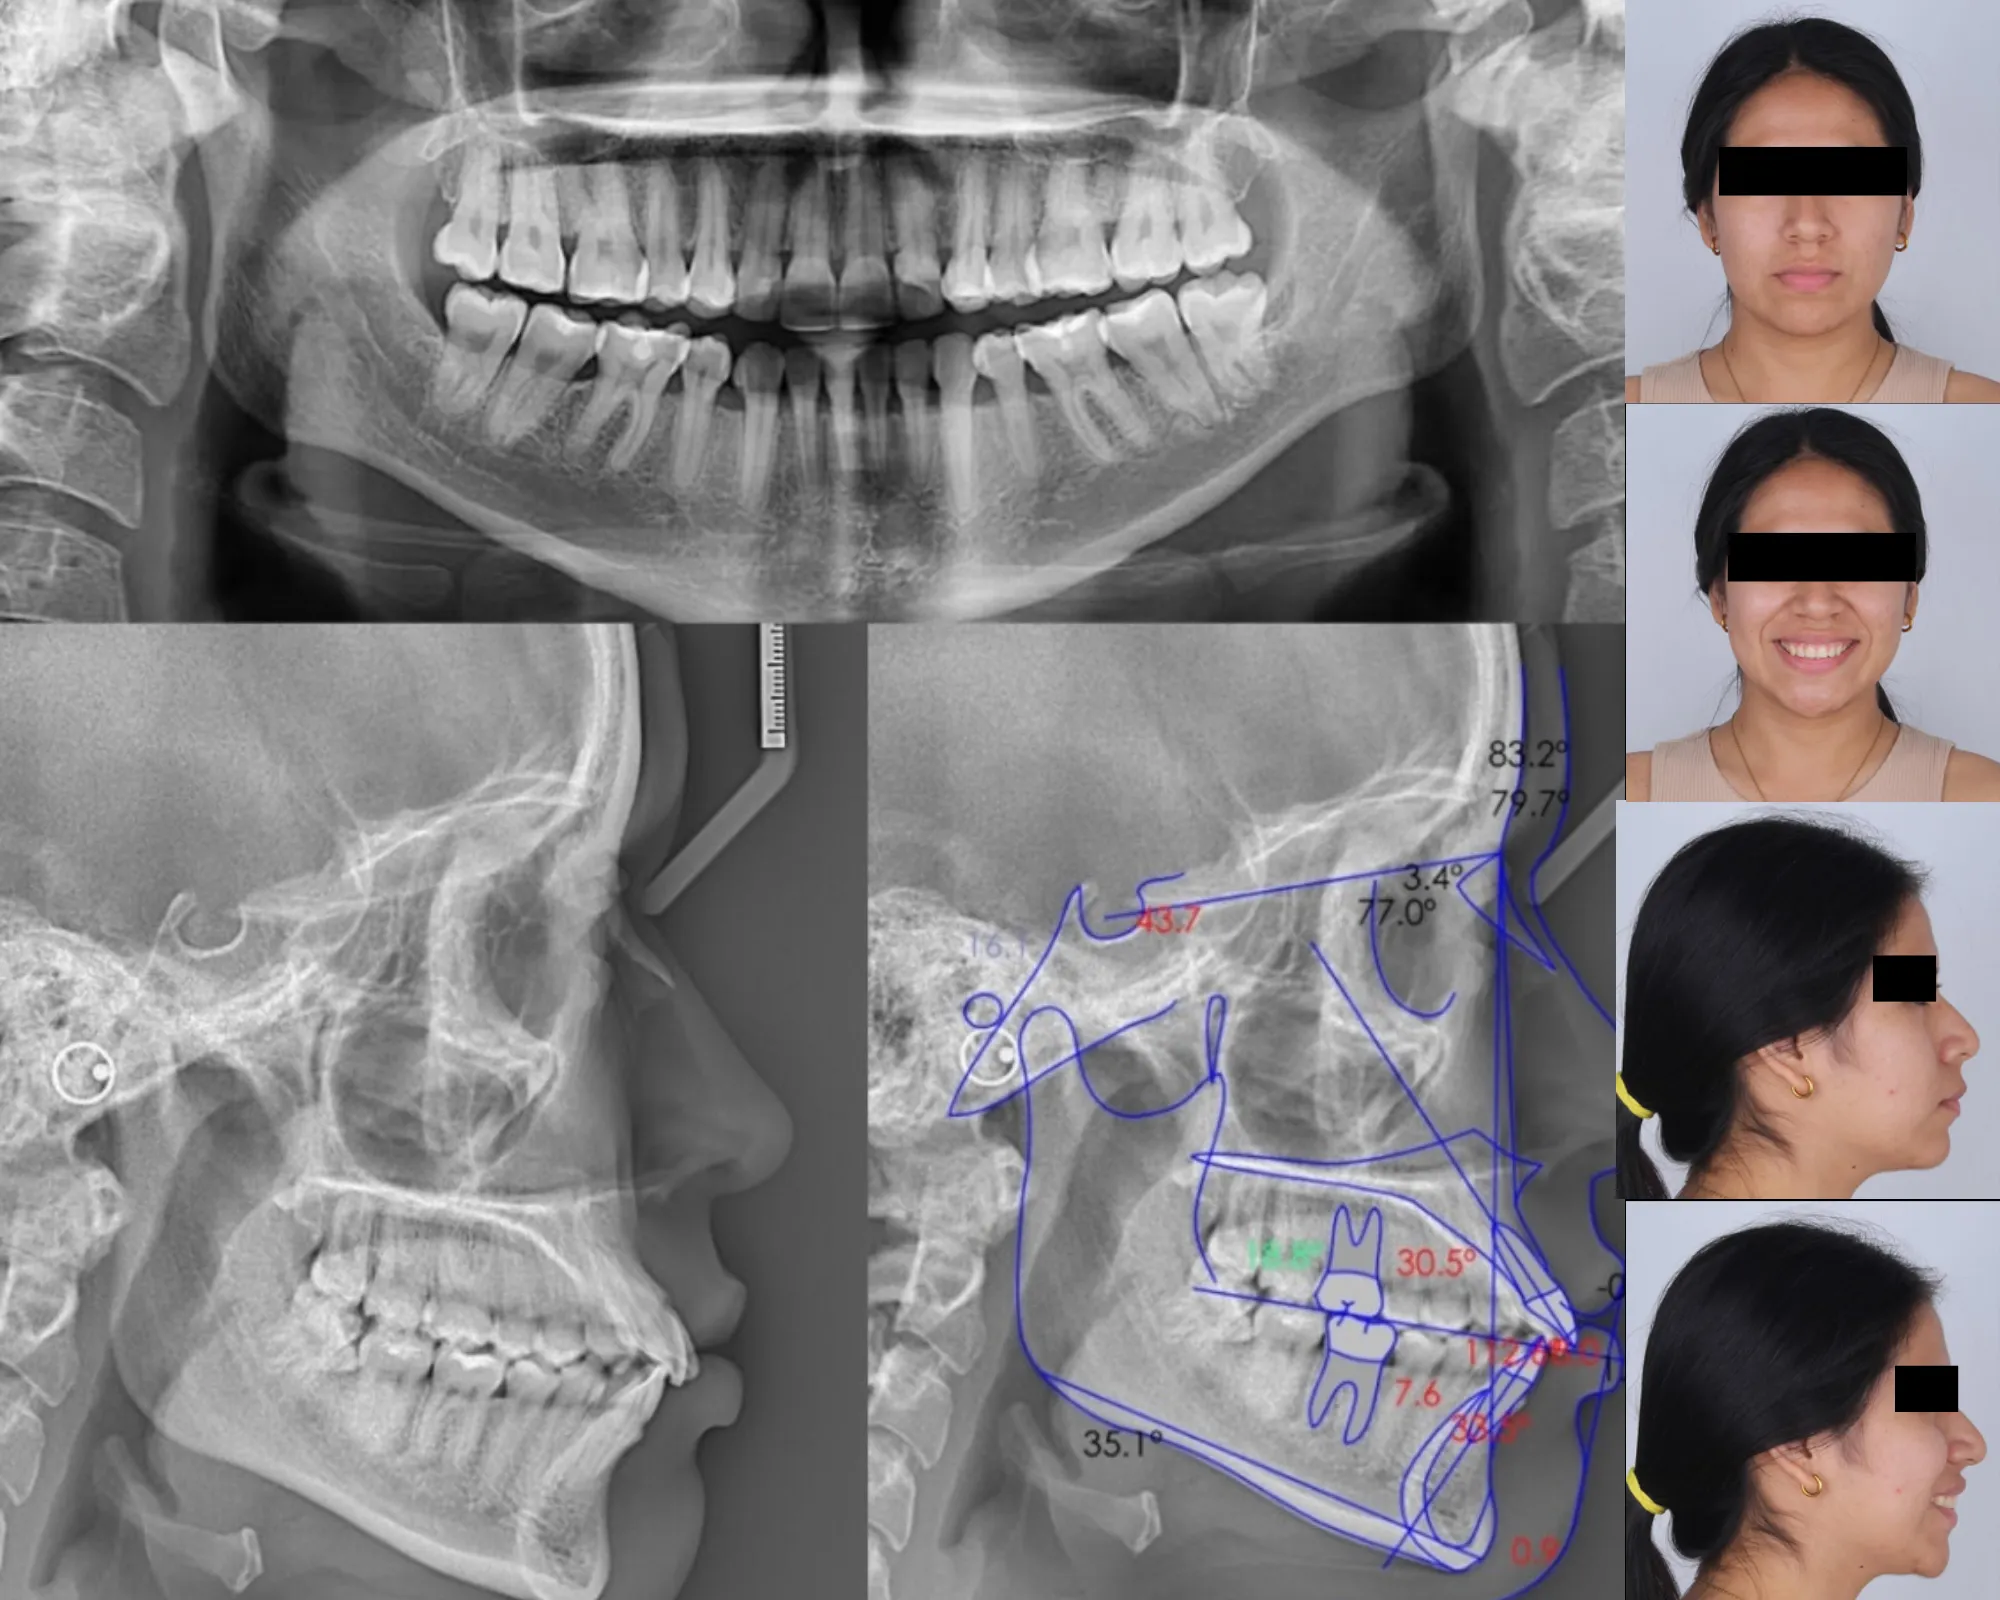

ANÁLISIS CEFALOMÉTRICOS

Nuestros especialistas hacen uso de sistemas de radiología digital de última generación para proporcionarle análisis de ortodoncia y cefalometría de la más alta calidad. Contamos con más de 30 análisis cefalométricos.

PAQUETE ORTODÓNTICO

Incluye: 02 Radiografías (panorámica y cefalométrica), fotografías extraorales, informe cefalométrico del análisis que se solicite (hasta 03 análisis).